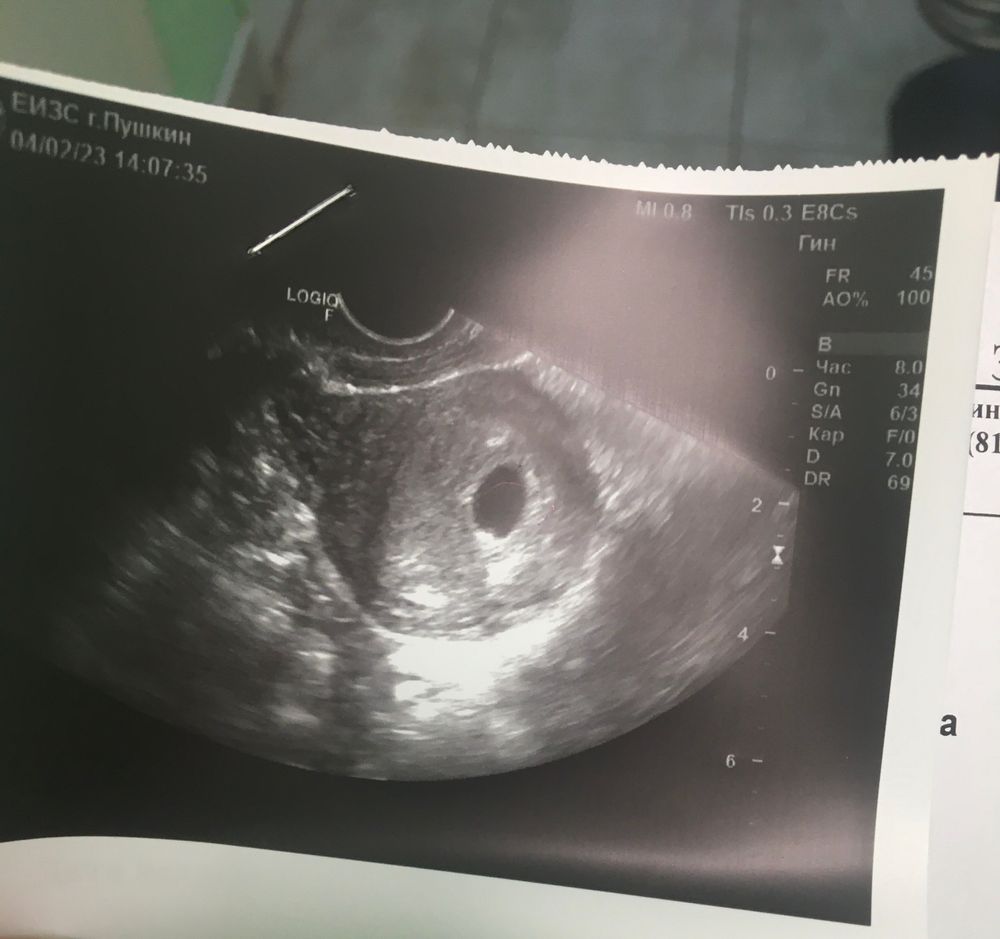

Ну вот, сбегала на первое УЗИ.

Считала акушерскими неделями, 8+6

По размерам 4 недели с хвостиком 🥰 Закрепилось чудо моё получается 1-3 января, как раз когда заприметила необычные сгустки крови, спустя пару дней после овуляции. Теперь уж точно Новый год, мой самый любимый праздник ❤️

Когда услышала заветную фразу «Маточная беременность», аж растеклась от счастья на кушетке